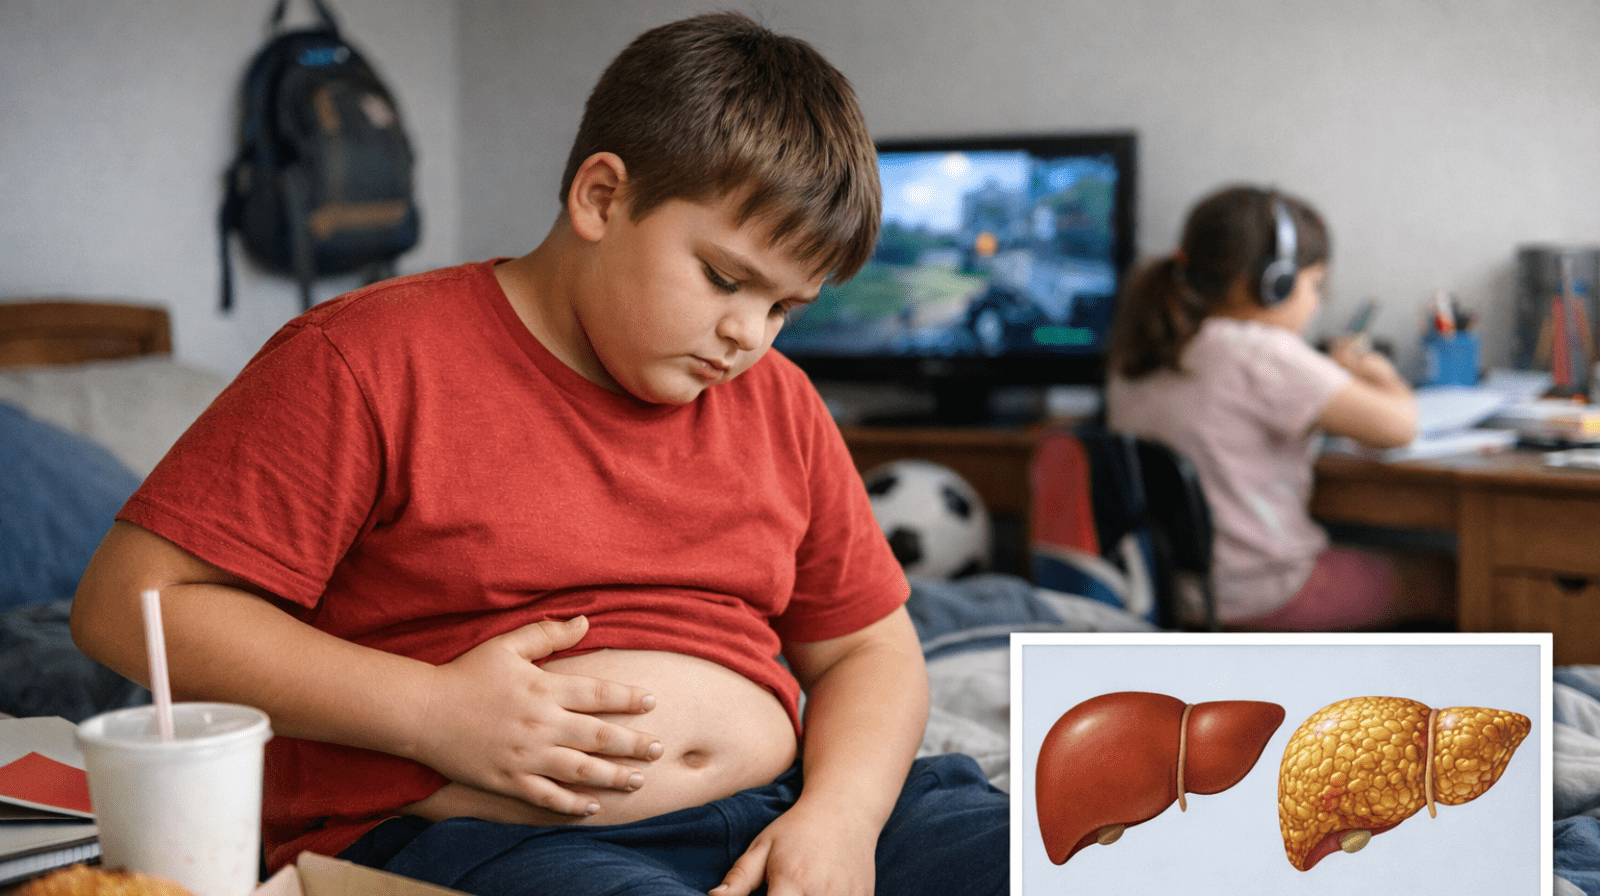

Non-Alcoholic Fatty Liver Disease is increasingly common worldwide and linked to obesity, diabetes, and metabolic syndrome. Recent research underscores that MASLD treatment centers on lifestyle modification and drug therapies targeted at metabolic risk factors.